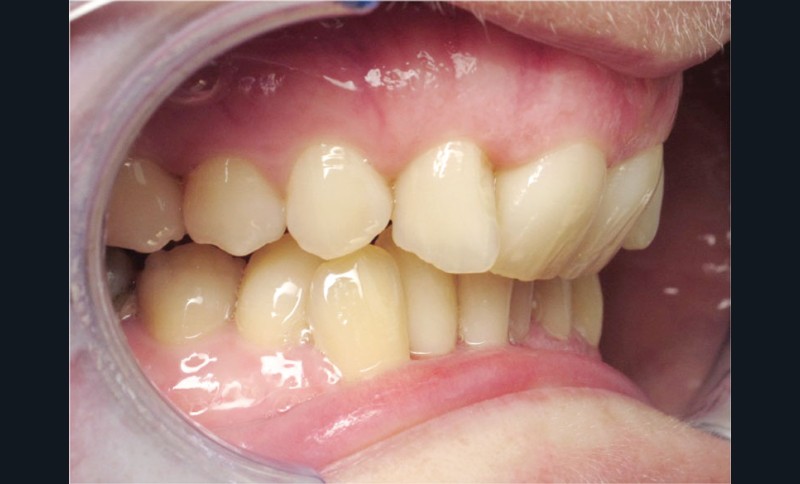

Cas n° 2

Nous lui avons donc proposé un traitement d’alignement avec maintien des 14 et 24 en position de 13 et 23 et optimisation du torque pour favoriser un développement des arcades et chercher à améliorer le sourire et le soutien labial.

La patiente donne son accord pour un appareillage Damon Insignia métal qui permet une individualisation complète des brackets dans les 3 sens de l’espace.

Un appareillage Damon métal a été mis en place, réalisé à partir d’un set up numérique Insignia pour obtenir un contrôle précis des torques et de la forme d’arcade et réduire le temps de finition grâce à un collage indirect très précis.

De larges surélévations postérieures étalées ont été mises en place et la patiente a porté des élastiques précoces suivant les principes de la technique Damon. Les 14 et 24 rempliront le rôle des 13 et 23.

L’objectif, en utilisant la technique Insignia est de réduire le temps de traitement de 28 à 18 mois avec 12 rendez-vous (fig. 5 à 14).